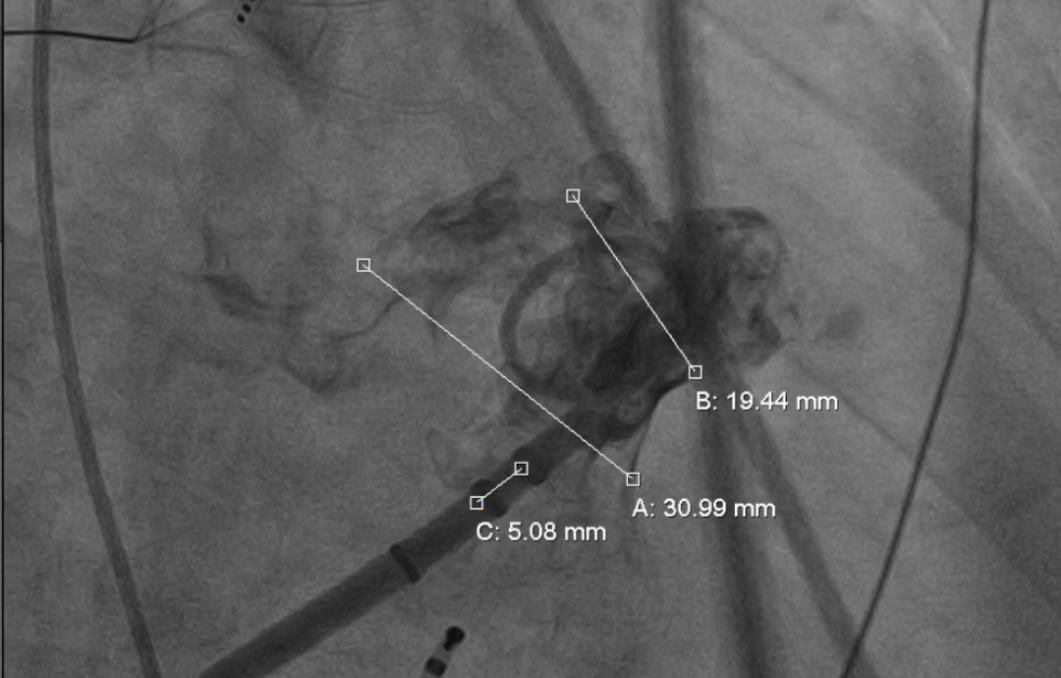

右肩位造影测量锚定区:19.44mm,开口部:30.99mm。

右肩位造影

肝位造影测量锚定区:21.62mm,开口部:29.3mm。选择LAMax LAAC® 2133 Plus型号左心耳封堵器。